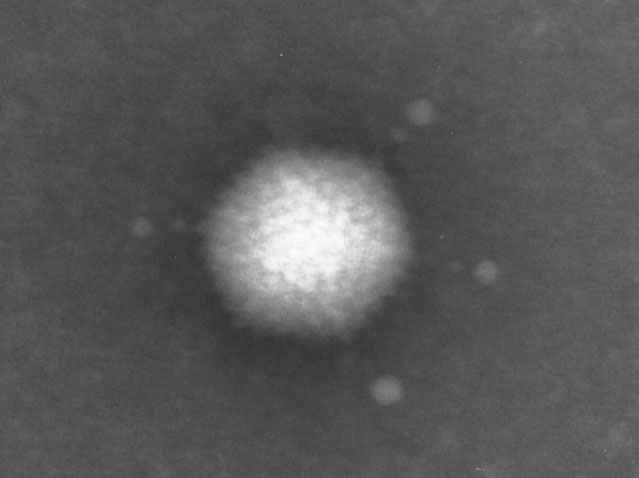

Immno-TEM